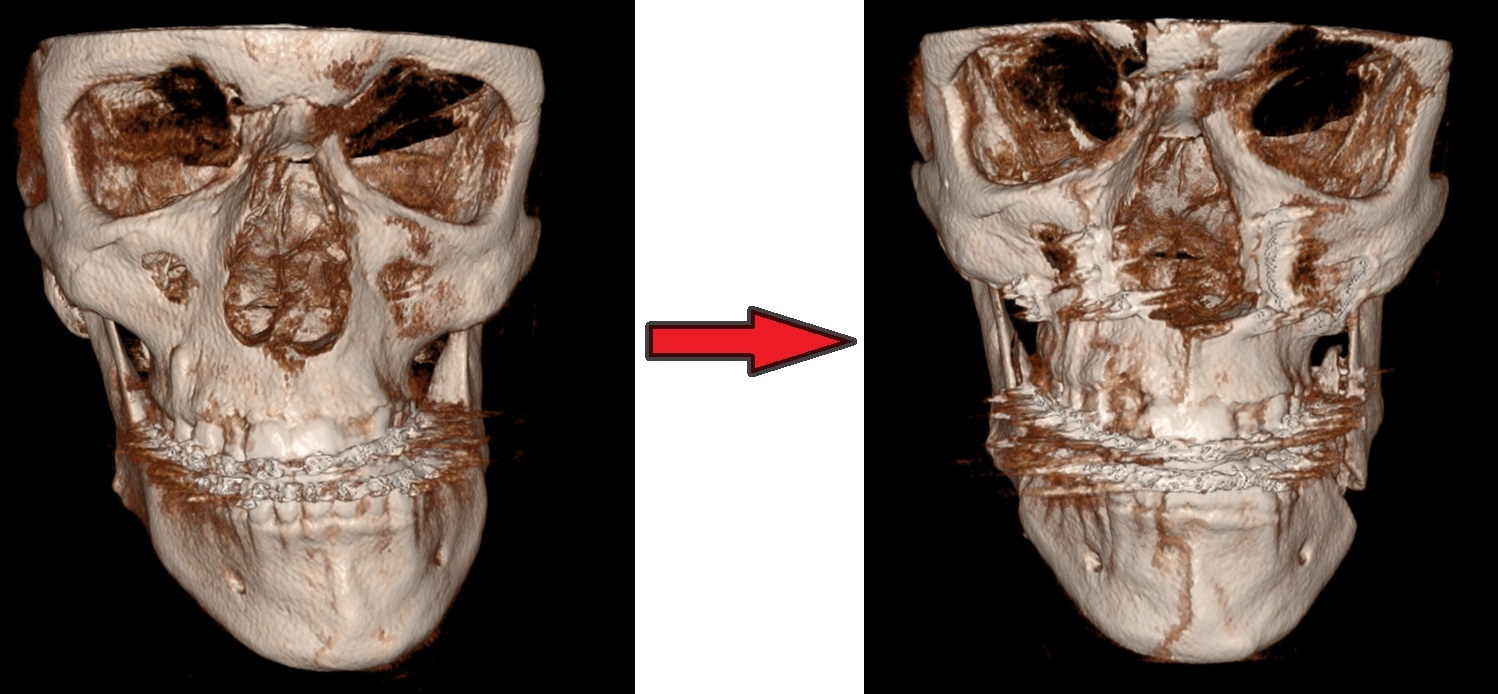

Asymmetrische onder- en bovenkaak, gecombineerde onder- en bovenkaaksverplaatsing(bimaxillaire osteotomie)

Röntgen beeld voor en na operatie